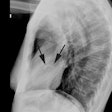

Anomalous RCA origin

from the left coronary sinus: The patient below underwent

coronary CT angiography to assess for coronary artery

disease. The patient was found to have an anomalous

RCA arising from the left sinus of valsalva. The

vessel can be seen to course between the pulmonary

trunk and aorta (black arrows) |